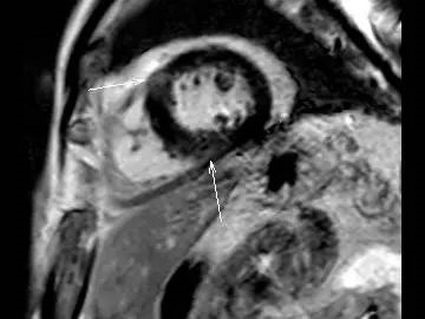

4.心肌的信号、强化是否正常。比如:炎症、水肿、纤维化、淀粉样变性、瘢痕、室壁瘤等。

3.心肌活性评估,心肌组织中失去活性的心肌细胞和延迟强化存在可靠的对应关系,即失去活性的心肌组织有延迟强化。

4.非缺血性心肌病的评估,如肥厚性心肌病、扩张性心肌病、限制性心肌病等,心肌呈现不同程度条状、斑片状、斑点状的延迟强化。